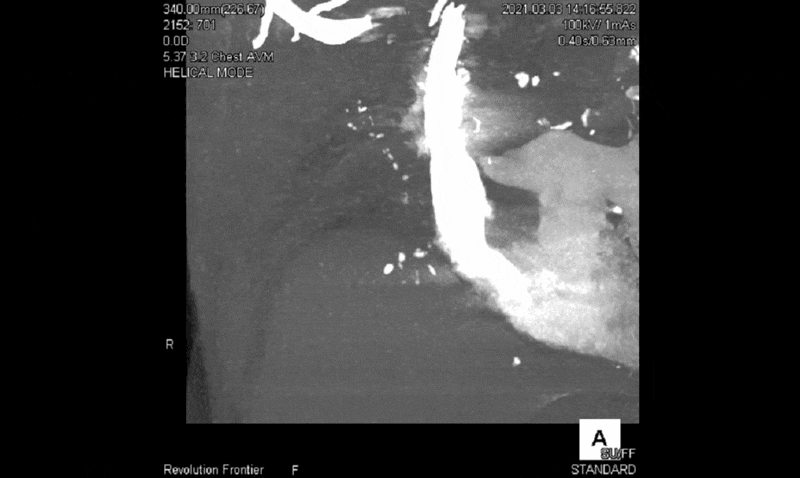

図2に撮影で得られた4D-MIP画像を提示します。肺動脈相で右肺動脈は描出されず、大動脈相で肋間動脈および右下横隔動脈の拡張を認めました。また右肺静脈が描出されるのと同時に、肺動脈の残余が逆行性に造影されたため、右肺動脈の血流途絶のため肋間動脈が代償的に肺を潅流していると考えられます(図2)。

図2 Shuttle画像の4D-MIP